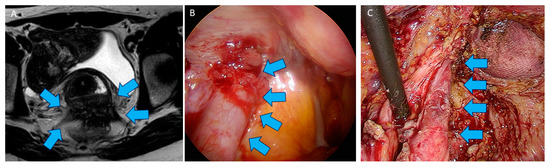

4. Shaving Technique: Surgical Procedure

4.2. Surgical Technique